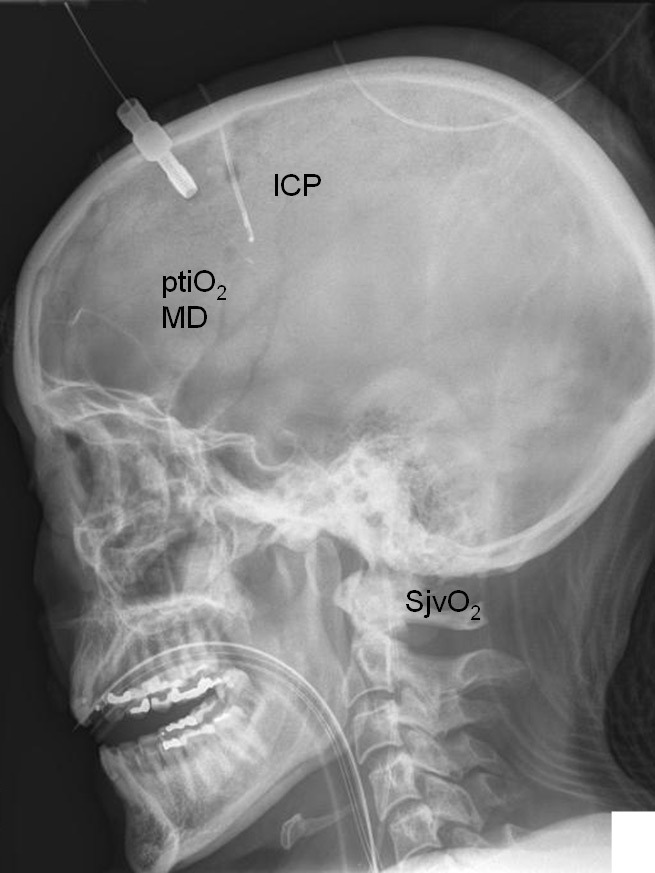

Basic treatment aims in patients suffering from severe TBI are to optimise cerebral perfusion, improve oxygenation and stabilise metabolism in order to prevent secondary progression of underlying brain damage. For this, integration of extended neuromonitoring in our daily clinical routine appears helpful. Extended neuromonitoring may provide more detailed insight into otherwise occult changes. For this, SjvO2, ptiO2, microdialysis, TCD and electroencephalographic studies provide important data enabling characterisation of functional influences defining threshold values and the adaption of therapeutic interventions in type, extent and duration (fig. 1). These monitoring modalities aid in preventing excessive therapeutic corrections which by themselves can induce additional damage. In this context, aggressive volume administration to increase CPP has been associated with a sustained risk of ARDS [46] and abdominal compartment syndrome [47], excessive ventilatory support to increase paO2 is feared to induce additional pulmonary damage [48], aggressive lowering of arterial blood glucose to prevent hyperglycaemia- induced cell damage increases frequency and extent of hypoglycaemic episodes [49], and a categorical transfusion regimen to improve cerebral oxygenation is offset by transfusion- related complications [50].

Figure 1

Illustrative lateral X- ray view showing positioning of ICP, ptiO2, microdialysis (MD), and jugular venous catheter allowing measurement of SjvO2. This allows to combine local (ptiO2, microdialysis) with global neuromonitoring (SjvO2).